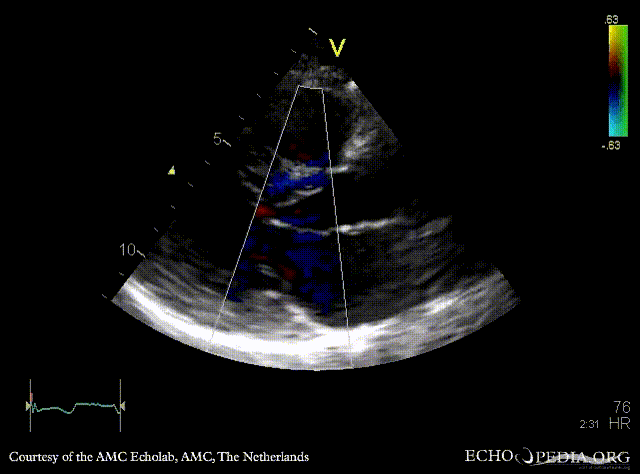

PLAX: concentric hypertrophy of left ventricle, SAM of AMVL PLAX with Color Doppler: high velocity turbulent flow in LVOT